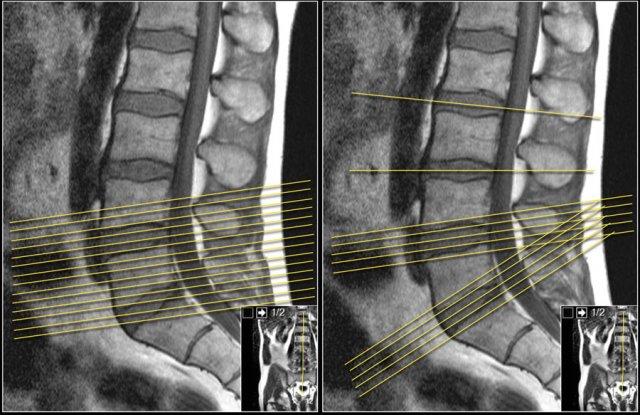

Tốt hơn nên sử dụng các lát cắt liên tục với cùng một góc nghiêng, song song với tầng nghi ngờ có chèn ép thần kinh.

Cách này có ưu điểm là cho phép theo dõi toàn bộ đường đi của rễ thần kinh liên quan qua bốn tầng có thể xảy ra chèn ép.

Khi khảo sát nhiều tầng với các góc nghiêng khác nhau như trong ví dụ bên phải, sẽ không thể theo dõi toàn bộ đường đi của rễ thần kinh và không có được cái nhìn tổng thể.